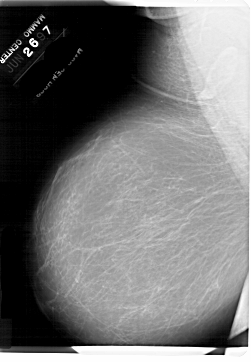

A_1796_1.LEFT_MLO

LEFT_MLO LINES 6871 PIXELS_PER_LINE 4756 BITS_PER_PIXEL 12 RESOLUTION 43.5 NON_OVERLAY